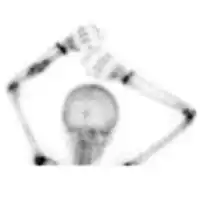

X-ray and CT scan show lytic expansion lesions with clear borders.[1] Expansion of cortex gives the lesion a balloon-like appearance. Larger lesions may appear septated.[10] MRI reveals fluid levels.[1] Bone scan shows outer radiotracer uptake, with a central dark area.[1]

DSA: ABC of shoulder -

Bone scan: ABC left radius